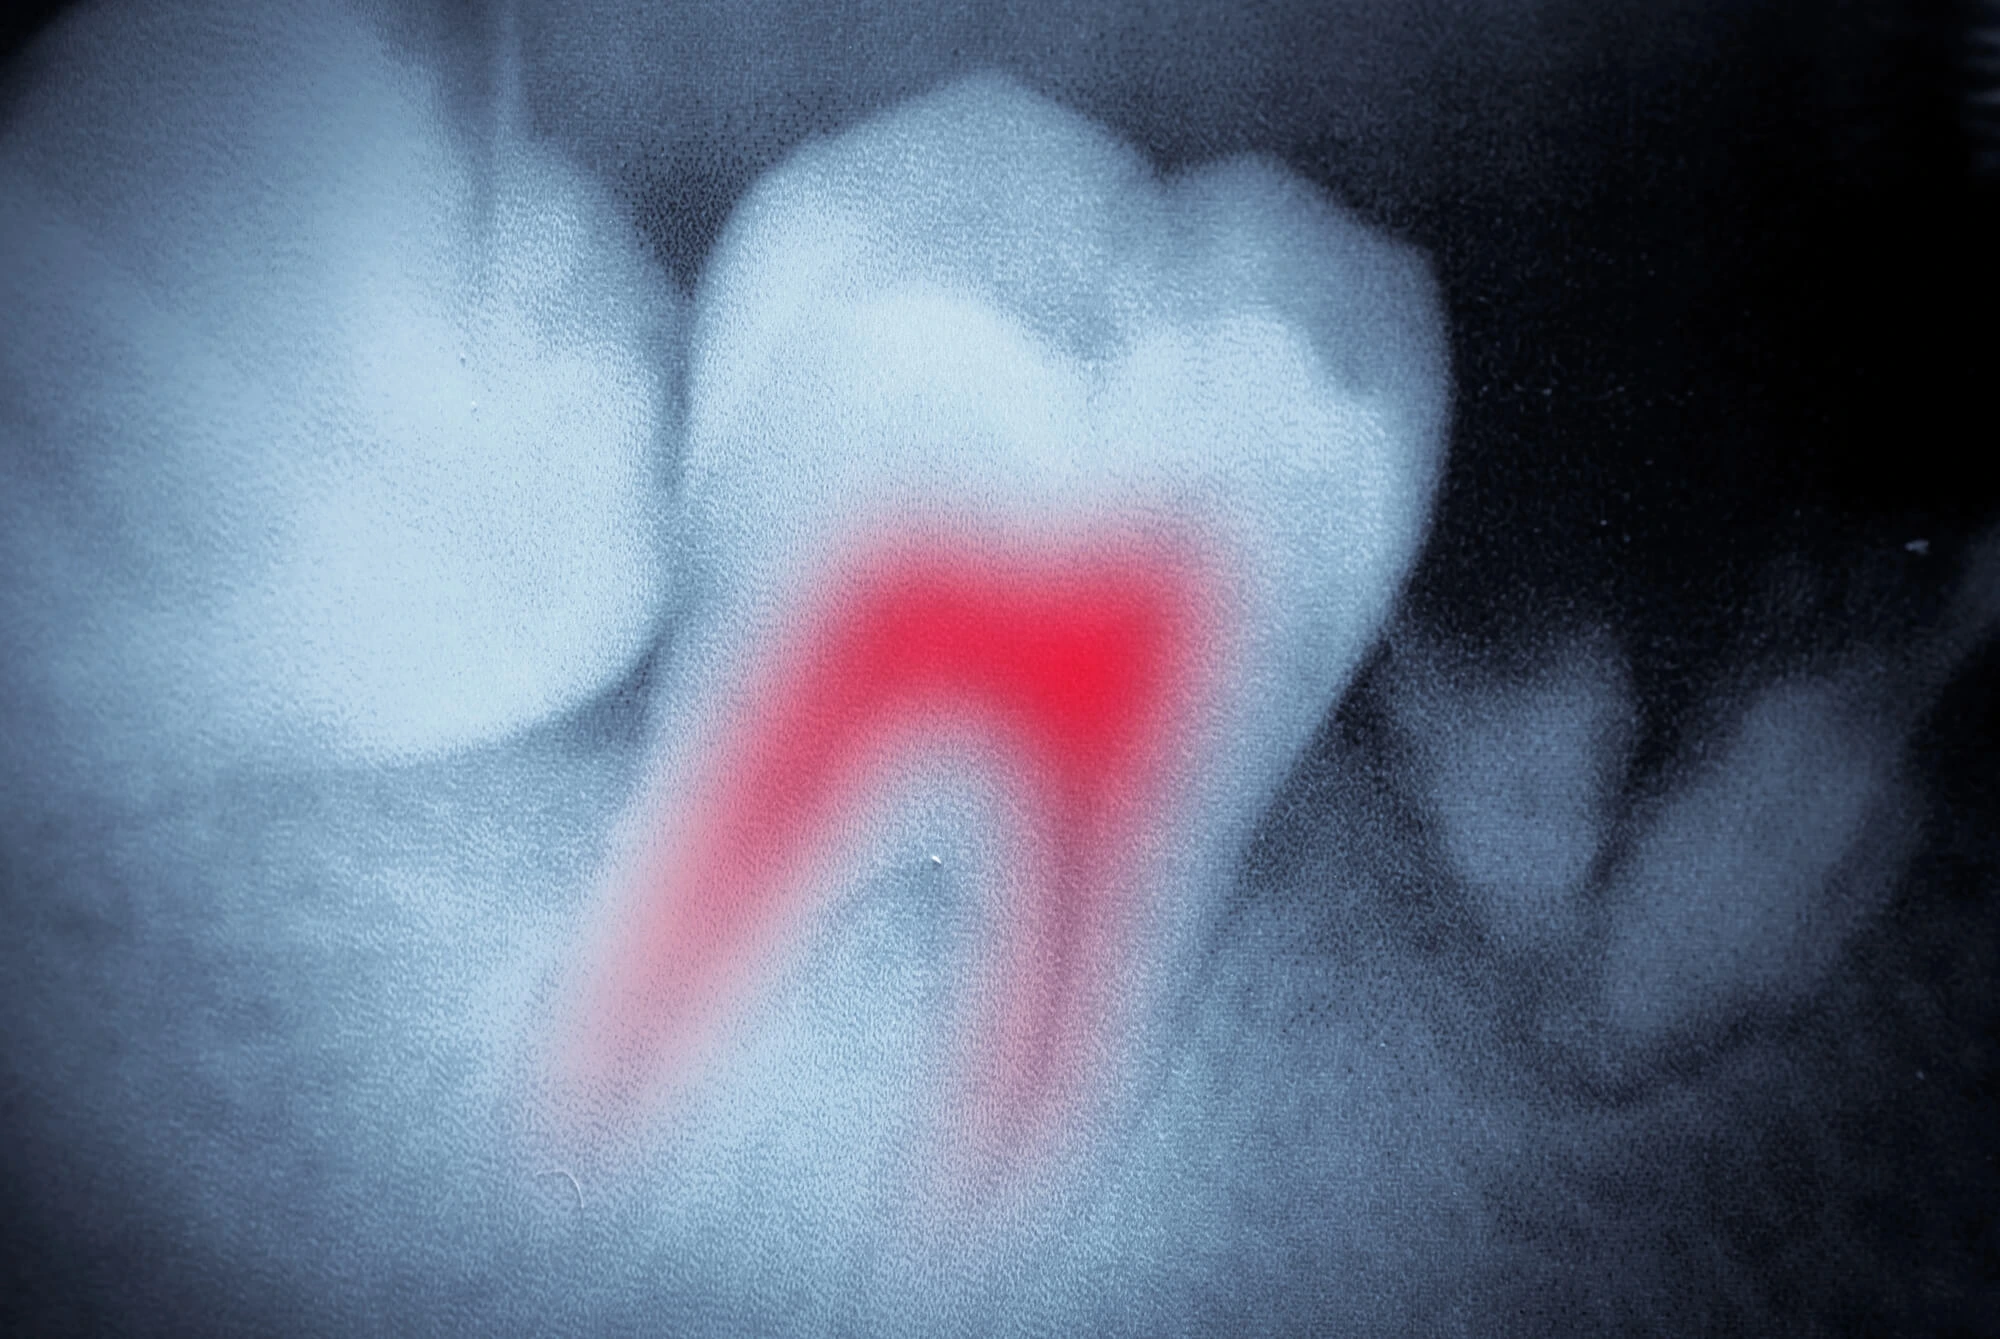

Root Canal Treatment

At LA Dental & MedSpa, root canal treatment is performed with precision, advanced technology, and a focus on patient comfort. When infection or inflammation reaches the inner pulp of a tooth, timely intervention is essential to eliminate pain and preserve the natural tooth structure. Our approach is designed to restore health while maintaining the integrity and strength of your smile.

Patients searching for a trusted Dentist Naples, FL often worry about discomfort associated with root canal therapy. Modern techniques and anesthesia have transformed this procedure into a highly effective and comfortable solution for saving damaged teeth. By carefully removing the infected tissue, disinfecting the canal system, and sealing the tooth, we stop the spread of infection and protect surrounding structures.

We begin with digital imaging to locate infection, assess the roots, and plan the procedure with precision.